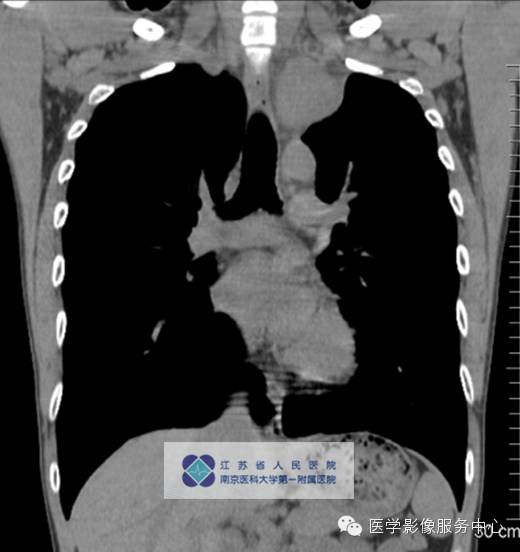

男,27岁,因“查体发现纵隔占位三月余”入院。

影像分析:左上、后纵隔内见类圆形软组织密度增高影,密度尚均匀,边缘清晰,增强扫描均匀强化。

本病可发生于淋巴结的任何部位,以纵隔淋巴结最为好发(约占60~70%),颈部(约占lo~15%)、腹部、腹膜后、盆腔等(约占1 0~1 5%)亦可发生。

单中心型:大部分为透明血管型,表现为纵隔及肺门圆形或卵圆形较大软组织肿块,边缘光滑锐利可有分叶,多数密度均匀可伴斑点状、树枝状等不同表现钙化。Meador等报道病变强化与病灶大小有关,小于5cm多为均匀强化,大于5cm的多不均匀强化,另外,还与病变的组织学特点如变性、坏死、纤维化的程度有关。